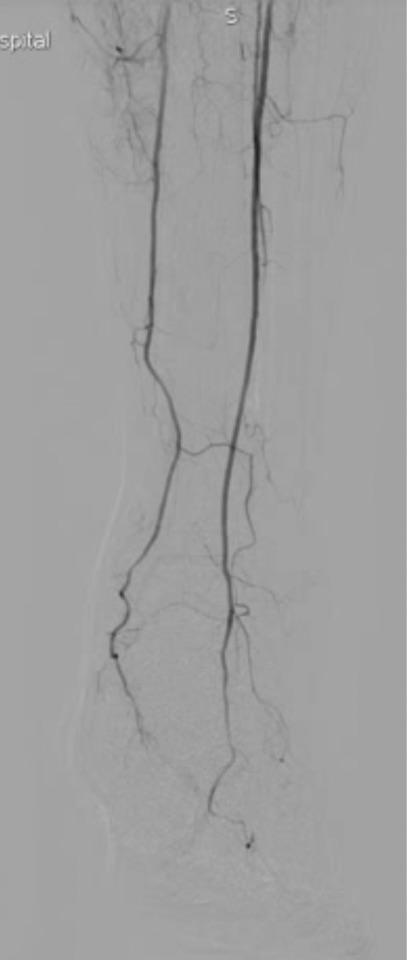

下面是术中dsa造影血管堵塞的情况

最后的结果令人满意,而且达到了患者的诉求,尽量不植入支架,来看看最后的造影结果吧